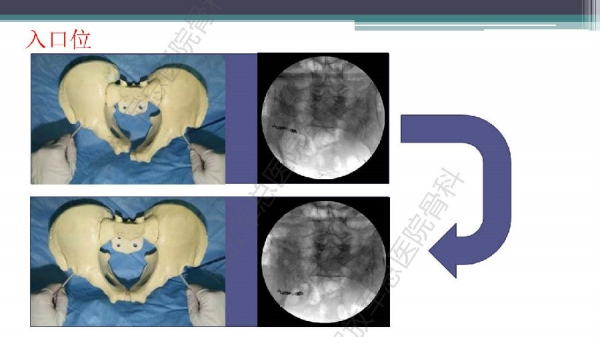

随着建筑和交通运输业的快速发展,合并骨盆、髋臼骨折多发伤、复合伤患者逐年增加,病死率和致残率都非常高。由于多发伤及复合伤、休克等往往不能在急性期对骨盆骨折进行确切复位及内固定,导致陈旧性骨盆骨折畸形愈合,从而产生一系列严重并发症,并且畸形矫正手术难度大、风险高、效果差。因此在抢救复苏后能不能尽早地、小切口甚至不切开、精确复位与固定骨盆骨折,防止陈旧性骨盆畸形愈合形成,成为广大骨科医生的挑战。解放军总医院创伤骨科在骨盆、髋臼骨折微创治疗方面做了一些工作,从微创理论探讨、到手术方法的改进,乃至钢板螺钉、微创复位器械等相继研发,形成了一系列的解决方案和配套内固定产品,为骨盆髋臼骨折的微创治疗奠定了基础。本幻灯则通过一例陈旧骨盆骨折畸形愈合的复杂治疗做引,通过介绍骨盆空间移位方式、透视特点、骨盆随意外架复位系统、复位原理以及1例典型病例的具体实施方案来综合、全面介绍我院微创骨盆髋臼骨折复位、固定新技术。